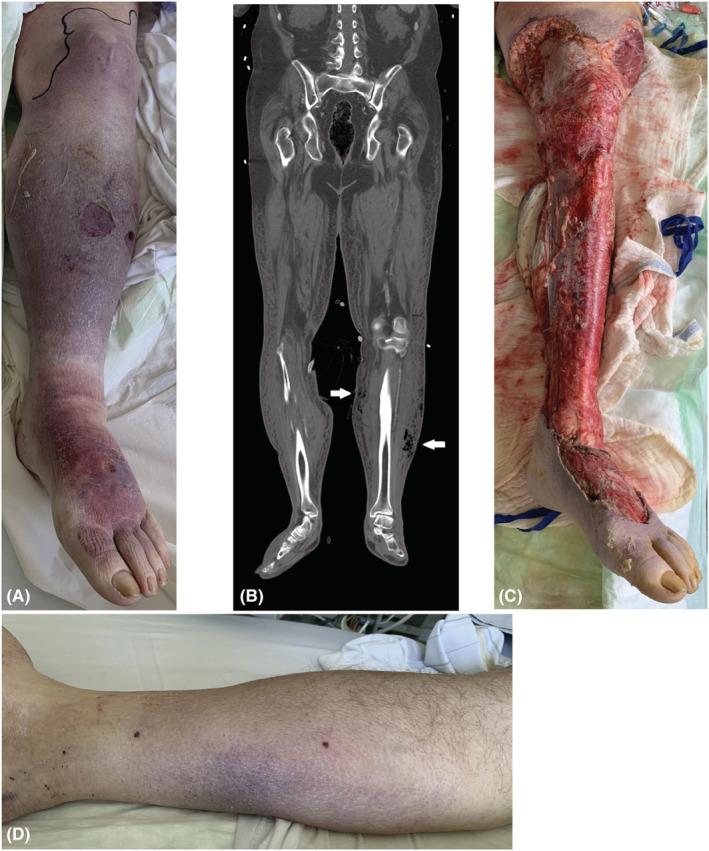

双侧非连续性下肢坏死性筋膜炎

Bilateral non-contiguous necrotizing fasciitis of the lower extremities.

Necrotizing fasciitis (NF) is an uncommon soft tissue infection. Multifocal-extremity NF is a rarity with high mortality rates. Herein we report a case of bilateral non-contiguous NF of the lower extremities due to with a fatal outcome, stressing the necessity of rapid and aggressive intervention in suspected cases.